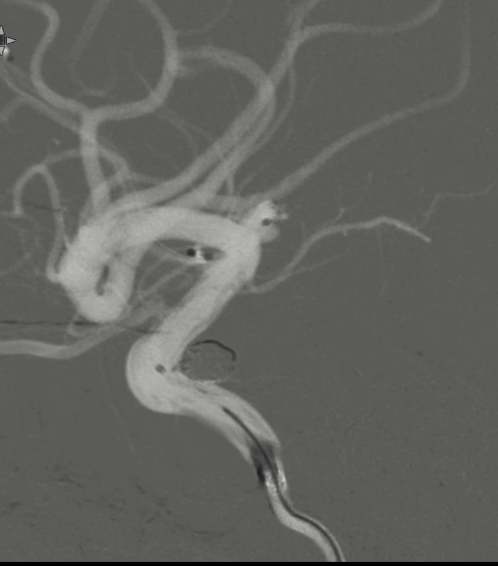

治疗结果

术后正侧位造影:Raymond Ⅲ级

术后支架重建:支架打开良好,近端Marker位于颈内动脉分叉处

术后Vaso CT未见出血,患者神清语利,神经系统查体阴性。